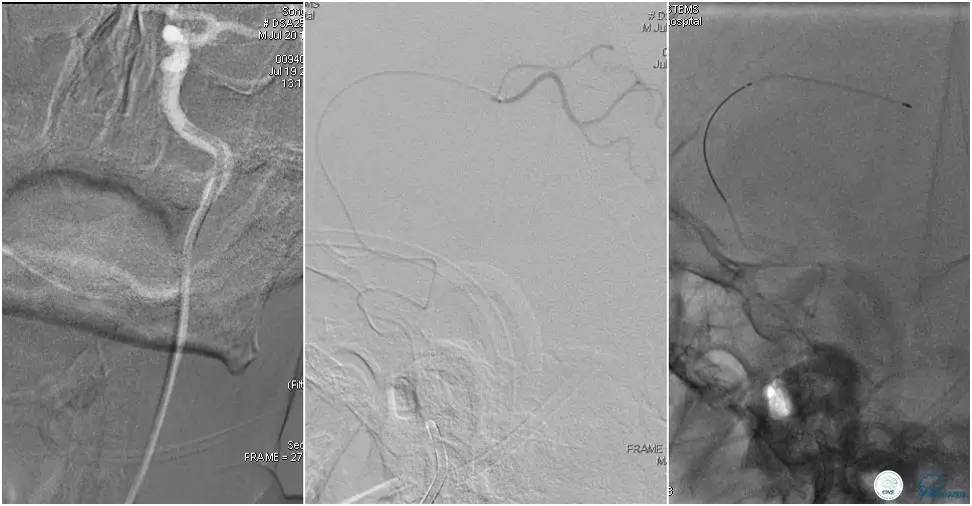

术后头颅CT复查。

术后复查头颅CTA。

术后复查头颅MRI。

术后第二天患者意识清,言语清,右上肢肌力1级,右下肢肌力3级,左上肢肌力5级,左下肢3级。

术后90天随访右上肢肌力3级,左上肢肌力5级,双下肢肌力4级,mRS评分3分。